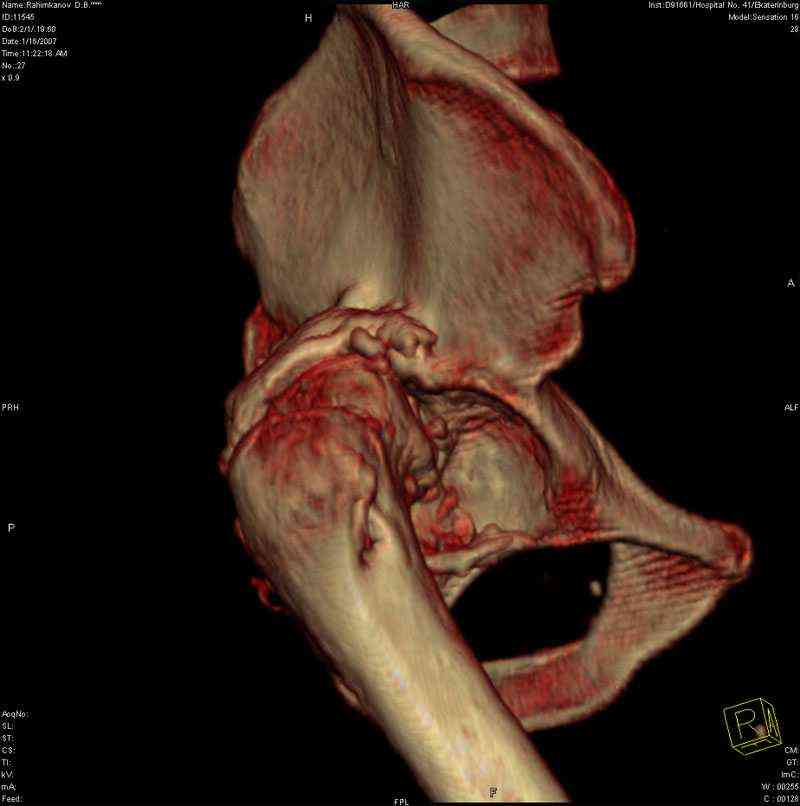

Застарелый вывих бедра

К нам обратился житель Казахстана с застарелым вывихом бедра.

Травма год назад, вместо синтеза заднего края казахскими умельцами установлена клинковая пластина, через 6 мес удалена. Больной ходит с тростью,сгибание в т-б 90, разгибание 170, укорочение 5 см, боли не выражены, анальгетиками не пользуется. Настроен на эндопротезирование в клинике, где есть опыт подобных операций (возможно за рубежом). Наш план: аппарат таз-бедро, постепенное низведение бедра, "октопус" с пластикой. Но с такими большими дефектами мы не сталкивались. Есть вариант сначала аппарат, затем реконструкция впадины, протез обычный через 4-6 мес. Есть мнение не восстанавливать длину. Будем признательны за полезные советы. Было бы интересно посмотреть пример.